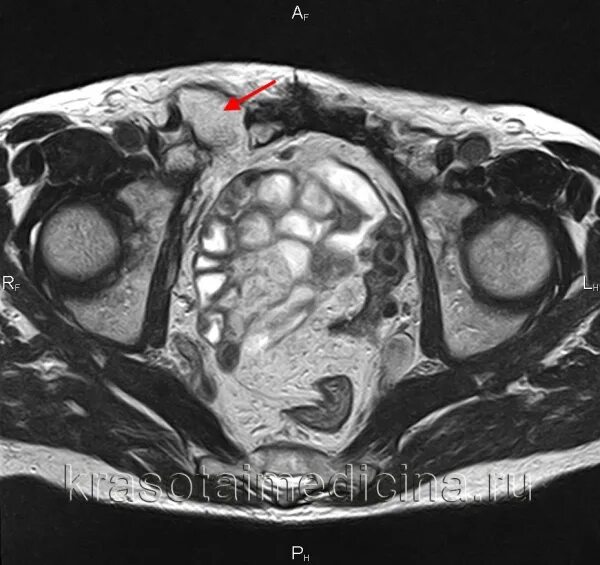

Паховая грыжа код мкб 10 у взрослых